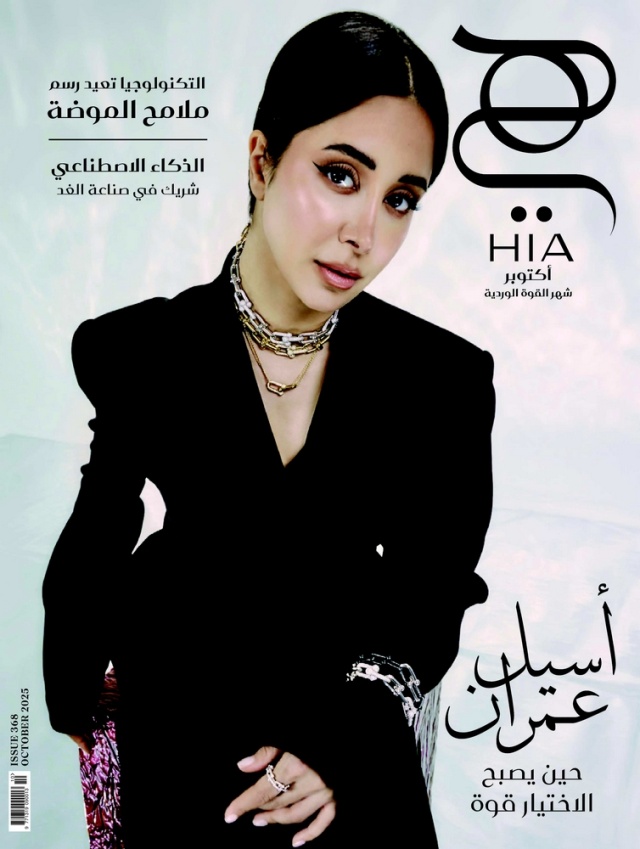

ولأهمية ذلك الموضوع، تقدم لك هي عزيزتي الحامل حقائق هامة عن علاقة الاسبرين بتسمم الحمل، من اسئلتنا المختارة التي تجيب عنها الدكتورة نجلة التميمي بمستشفى ميدكير الصفا أخصائيه نساء وولادة ..زميله الكليه الملكيه للنسائيه والتوليد بالمملكة المتحده